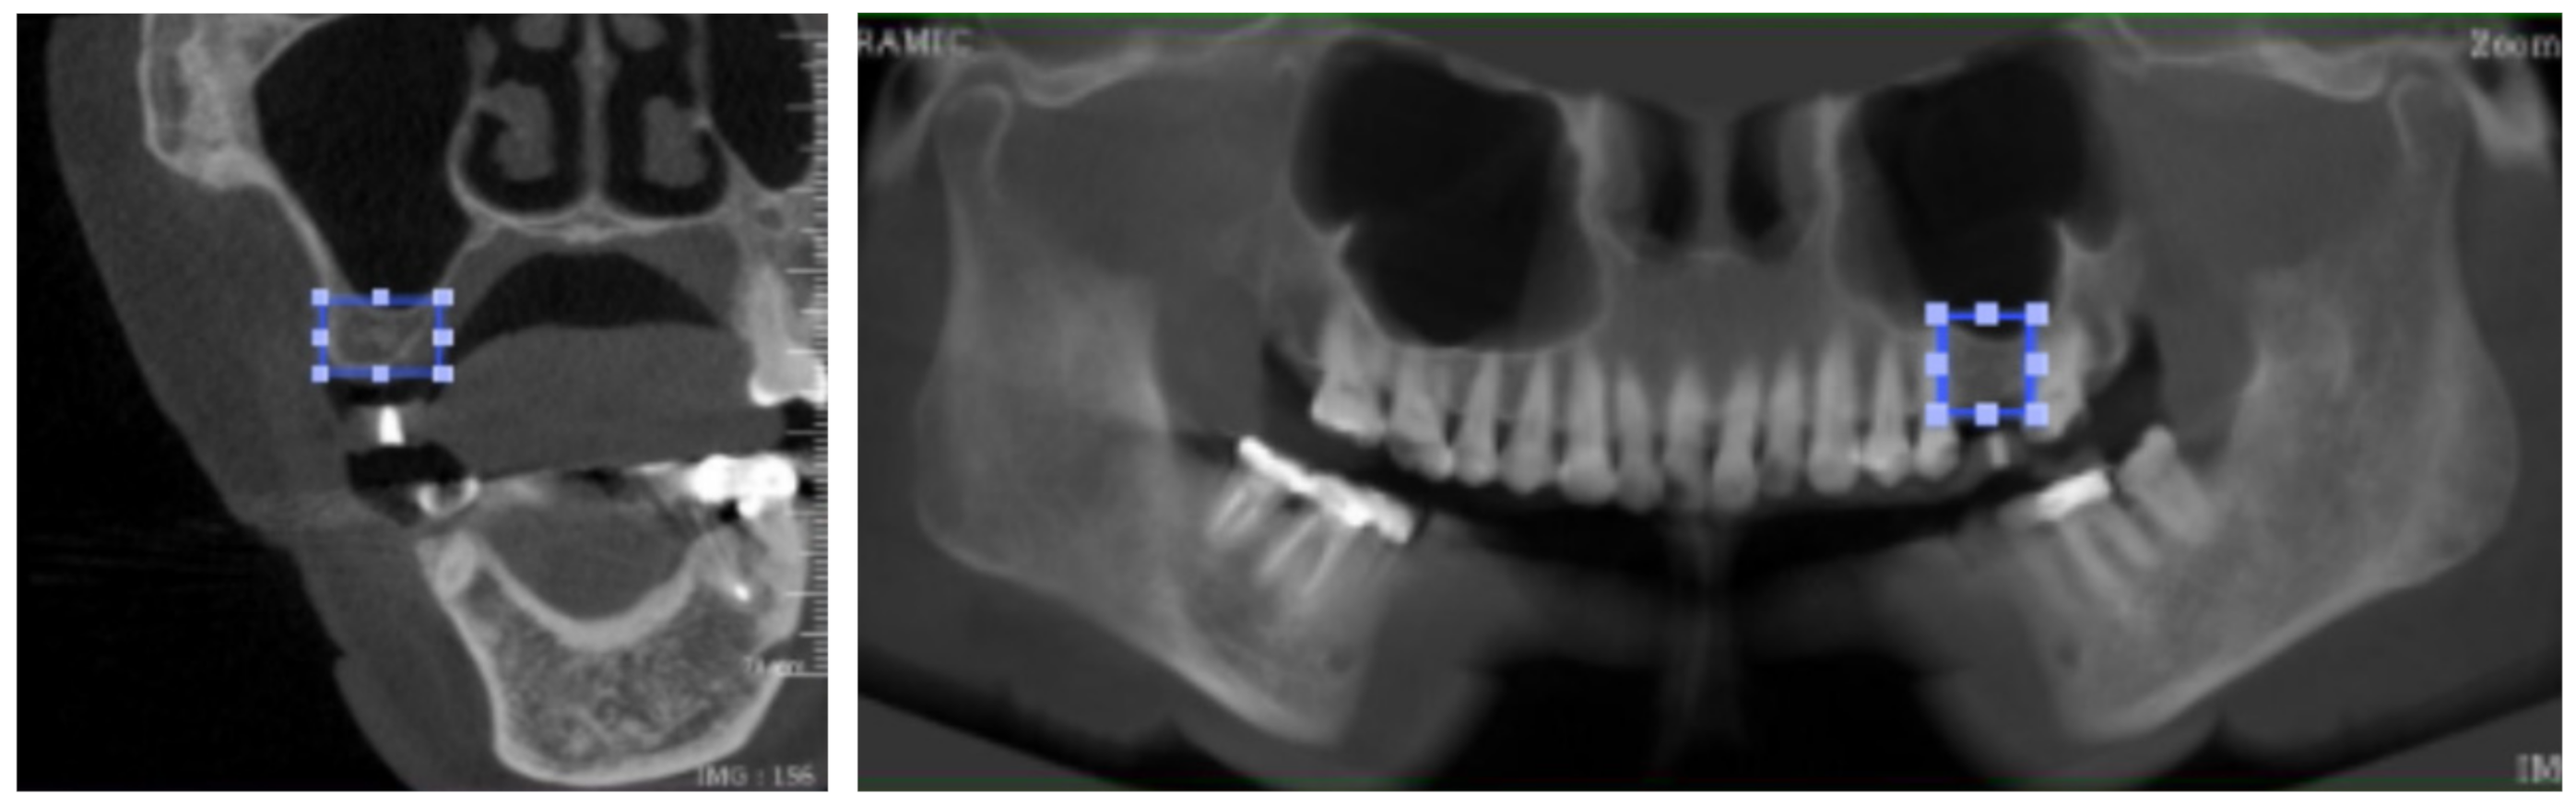

The labelled area in each image was generated in a square shape by connecting the four lines from the farthest border of the alveolar bone available for implant placement. The mentioned four lines included the upper border, lower border, mesial border, and distal border in a panoramic image, together with the upper border, lower border, buccal border, and lingual border in a cross-sectional image. The demonstration of the labelling process is displayed in Figure 2 and Figure 3a.

Figure 2.

Image labelling in both cross-sectional and panoramic images.